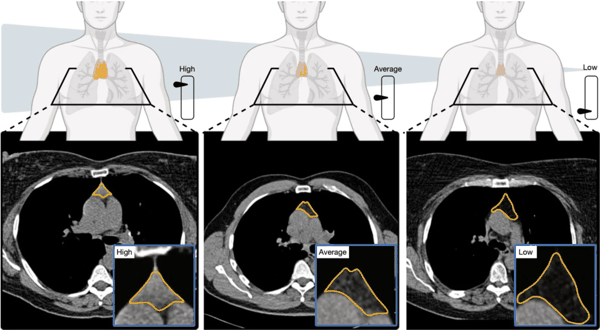

美国麻省总医院布里格姆分院的两项最新研究,颠覆了 “胸腺在童年后就不再重要”的长期认知。研究人员利用人工智能(AI)分析常规CT影像发现:胸腺更健康的成年人寿命更长,患心脏病和癌症的风险更低。另一项针对癌症患者的分析显示,胸腺状态还会影响患者对免疫治疗的反应效果——而免疫治疗正是依赖免疫系统发挥作用的核心疗法。

早期研究虽发现 T细胞多样性与衰老、免疫功能下降有关,但大多依赖少量血液样本。而这项新研究分析了超过25,000名成年人(来自美国全国肺癌筛查项目)和2500多名参与者(来自长期健康人群队列弗雷明汉心脏研究)的数据。

研究人员通过测量胸腺大小、结构和组织状态,创建了一个 “胸腺健康评分”。结果显示:

- 评分更高的人,死亡风险降低约50%

- 心血管疾病死亡风险降低63%

- 肺癌发生风险降低36%

在校正年龄和其他健康因素后,这些关联依然显著。